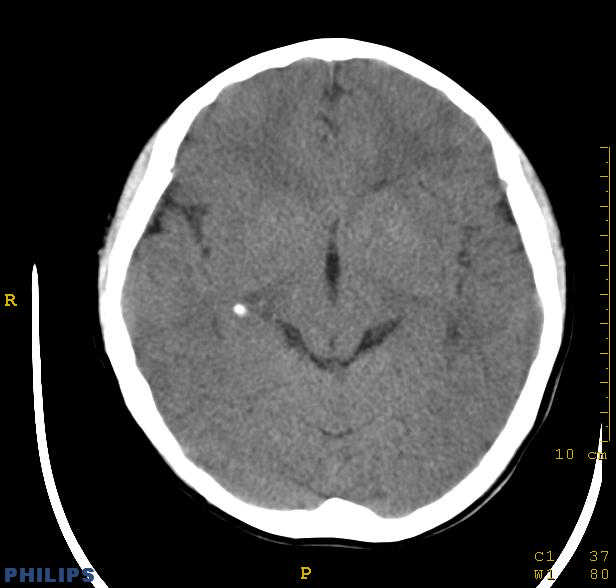

标题: PED0043:头颅平扫 男12岁.典型结节性硬化 [打印本页]

标题: PED0043:头颅平扫 男12岁.典型结节性硬化

典型结节性硬化

[影像学表现]

1.ct表现:

①室管膜下有多发性小结节状钙化影,也可为单发、不强化;小结节亦可未钙化;突入脑室可以强化;但有钙化者居多,颅内异常钙化高达90%。一般出生后2年即呈典型钙化。

③可见白质区脱髓鞘的低密度区。

④可伴脑灰质异位。